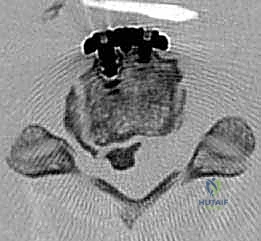

FIG 2 • D. Axial CT image demonstrating vertebral canal compression from large ossified posterior longitudinal ligament.